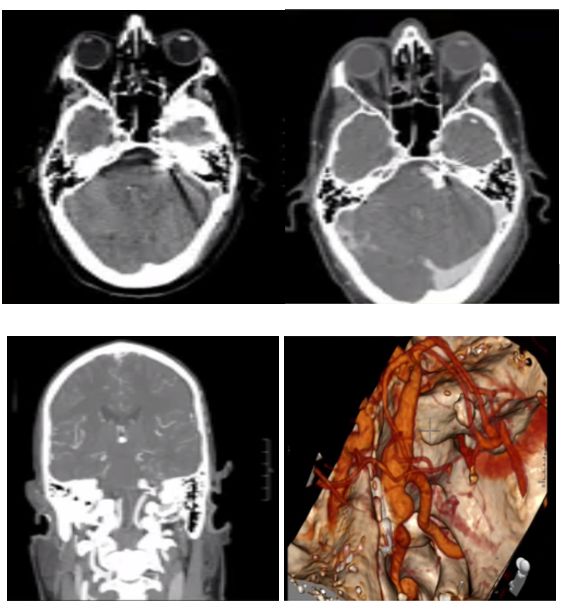

58岁男性患者,临床表现为左侧面肌痉挛,术前影像学检查诊断为基底动脉扩张延长症,导致左侧面神经受压(图1)。经患者同意后进行手术。手术采用远外侧入路,通过扩大枕下乙状窦后切口,显露基底动脉。基底动脉在中脑-脑桥连接处水平压迫左面神经根部。用muslin棉条制成悬带套住基底动脉,在斜坡硬脑膜上用19号针穿刺一孔;取一枚7mm直动脉瘤夹,将悬带末端栓系于动脉瘤夹一端,再将动脉瘤夹另一端穿入硬脑膜上破孔,把悬带锚定于硬脑膜上。通过拖曳悬带调整基底动脉的张力,最终将基底动脉从面神经上完全移开后,固定之(图2)。术后复查的CT及CTA显示,面神经不再受扩张、延长的基底动脉压迫(图3)。值得注意的是,由于手术野狭窄,在进行悬带套过基底动脉和移位的过程中,应避免过度牵拉致使穿支血管撕裂,一旦出血可能导致极其严重的后果。

图1. 左图:术前CT。右图:术前CTA。